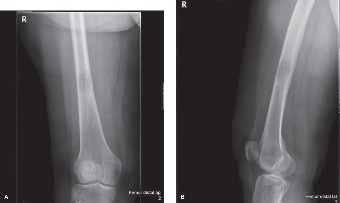

A 9-year-old, baseball pitcher presents to the office with 4 weeks of elbow pain of his throwing arm. He deni…